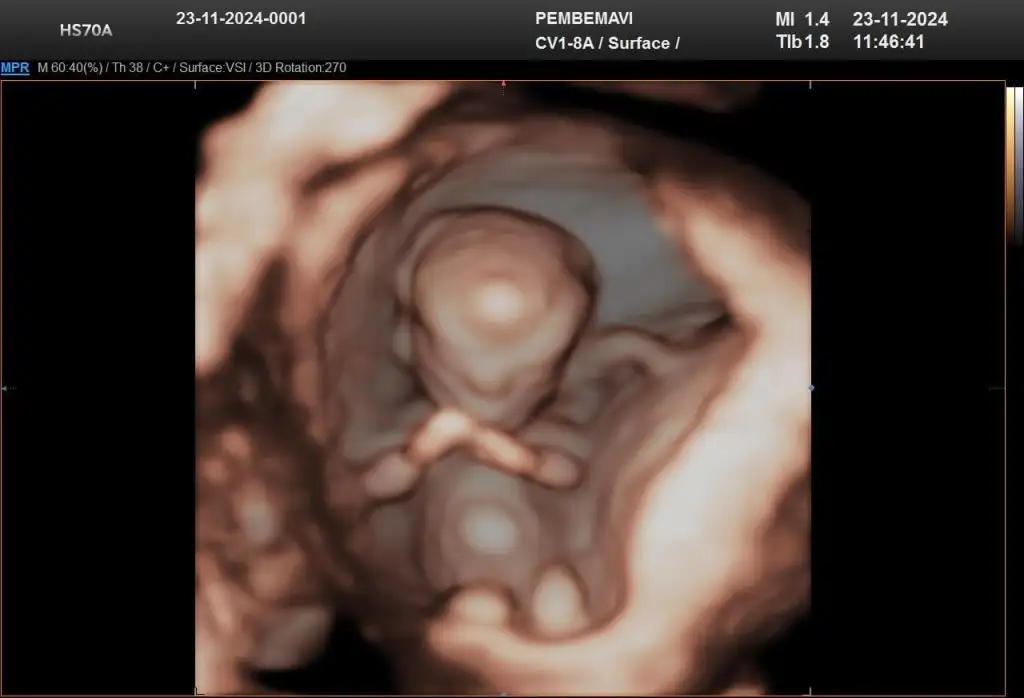

Renkli ultrason dediği ayrıntılı ultrasondur bence çünkü ben bu gidişimde de renkli ultrasona girdim 3 boyutlu foto aldım ama ayrıntılı olanı perinatolog yapıyor kadın dogumcu değil

Renkli doppler dediği ayrıntılı ultrason ve onu radyoloji uzmanı yani perinatolog yapıyor diye biliyorum ben 11. Haftada gittim kendi doktorum farklı bir cihazla bebeğin görüntüsünü renkli üç boyutlu gösterdi